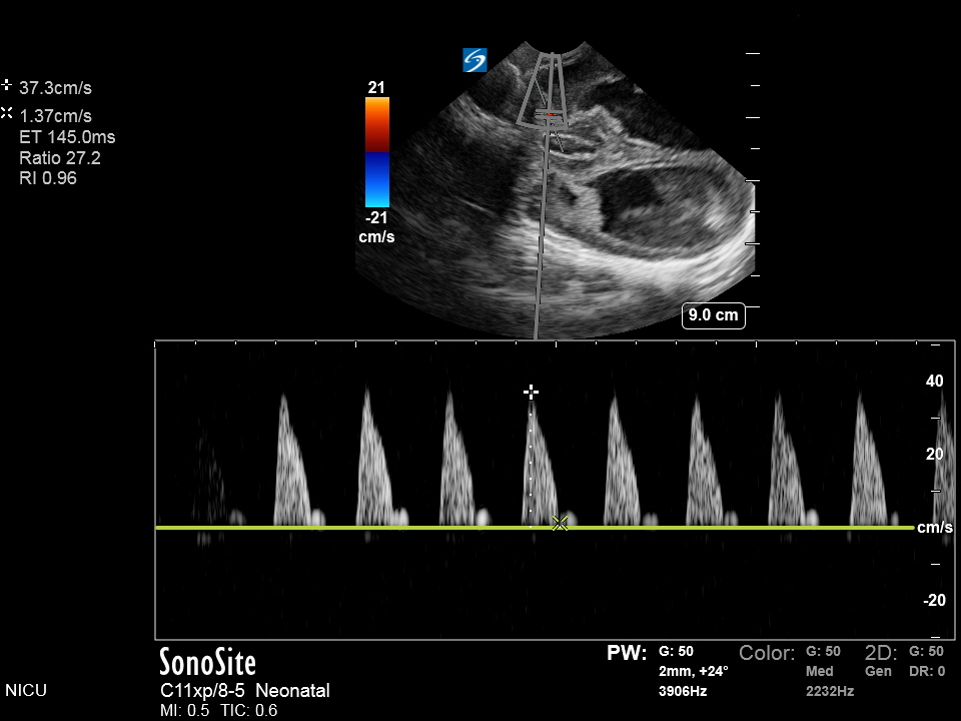

Neonatology Resistive Index 2 Image